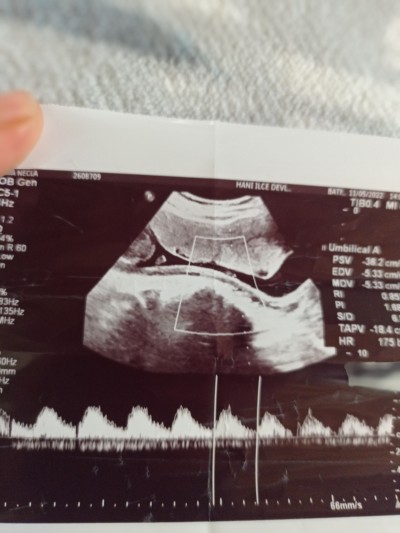

kızlar doktorum %80 kız dedi sizde bakar mısınız :)

Gebelik haftası 16